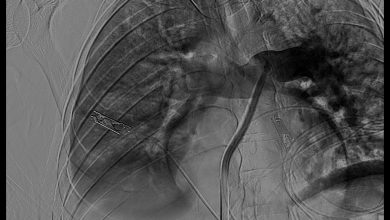

إنقاذ حياة شاب عشريني من نزيف حاد بالطحال عبر الأشعة التداخلية في «طبية مكة»

أسهم التدخل السريع ضمن نموذج الرعاية الصحية السعودي في إنقاذ حياة شاب يبلغ من العمر 28 عامًا، بعد تعرضه لإصابات…